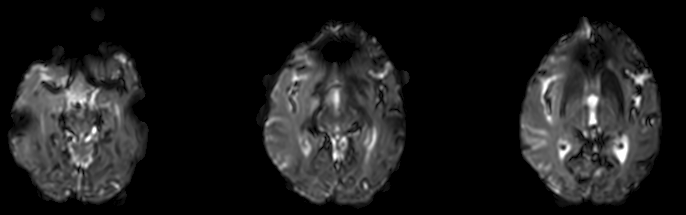

[Python] Brain MRI Thresholding 본문

What is Thresholding?

Thresholding is a type of image segmentation. It converts an image from colour or grayscale into a binary image that is simply black and white.

★ My application

extract brain region in brain MRI image to improve computational efficiency

3) generate binary removing noise

# generate mask

mask = np.zeros_like(tmp0)

for j in range(tmp0.shape[0]):

# mask[j] = tmp[j] > thr

mask[j] = closing(dilation(erosion((tmp0[j] > thr), se), se), se)'Programming > Medical Image Processing' 카테고리의 다른 글